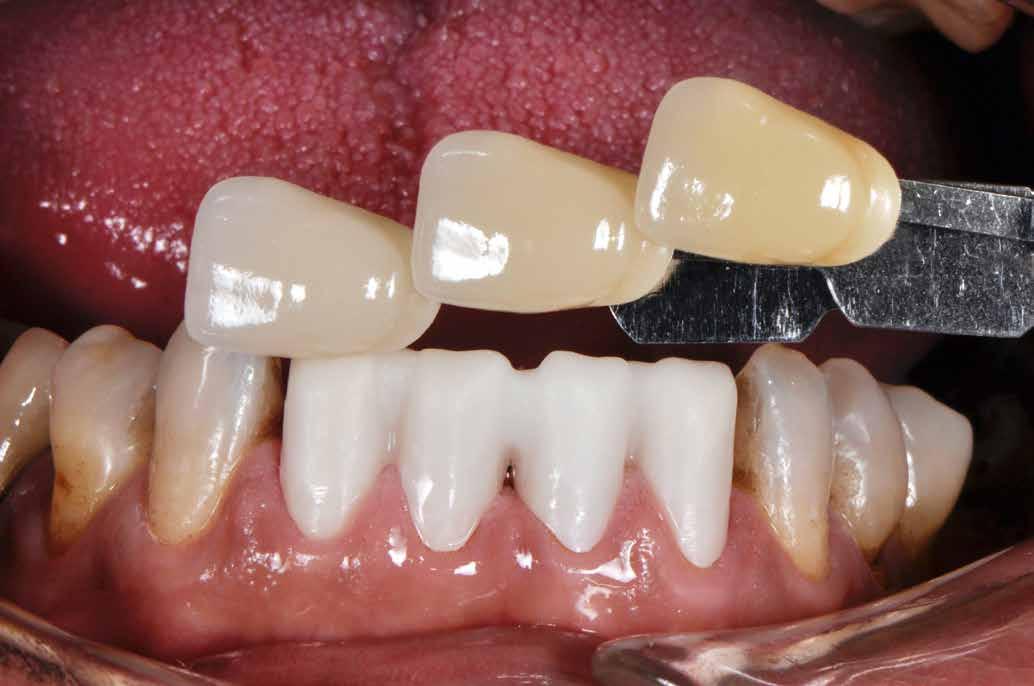

Ezt követően 6 hónapot vártunk a parodontális szövetek gyógyulásának érdekében. Ekkor a mock-up-ot felhelyeztük a páciens fogaira. Mivel a páciens elégedett volt a bemutatott látvánnyal, ezért a kezelés következő fázisának megkezdése mellett döntöttünk. A preparálás előtt a fogak felszínén mélységjelölő barázdákat alakítottunk ki (LVS1 FG Medium Depth Cutting Diamond 834.31.021, Brasseler Dental, One Brasseler Boulevard Savannah, Georgia 31419, Egyesült Államok). A megfelelő anyagvastagság biztosításához ezen felül egy 0,5 mm vastagságú átlátszó redukciós sablont (Keystone Industries, 480 South Democrat Road, Gibbstown, New Jersey, Egyesült Államok) is készítettünk. A sablont egy vákuumkészülék (Pro-Vac Machine 110V, Keystone Industries) segítségével hoztuk létre. A protetikai fázis során a frontfogak és az első kisőrlőfogak kerámia héjakkal történő ellátását terveztük. A preparálás mélységét a sablon felhelyezését követően, a sablonon lévő perforációk segítségével tudtuk ellenőrizni. A nyílásokba parodontális szondát vezettünk, hogy meghatározzuk a redukció mértékét (6. ábra). A preparálás megfelelőségét ezen felül egy gyúrható szilikonból készült sablonnal is ellenőriztük. Ebben az esetben is parodontális szondát használtunk a mélység ellenőrzése céljából (6. ábra). A csonkelőkészítés utolsó lépéseként a lecsiszolt fogfelszíneket polírkorongok segítségével (OptiDisc, Kerr, Orange, Kalifornia, Egyesült Államok) simára políroztuk. A lenyomatvétel során duplafonalas lenyomatvételi technikát alkalmaztunk. Az ínybarázdákba először #00-

8. ábra. Az ultravékony héjak adhezív módszerekkel történő ragasztása. (A): Az elkészült héjak. (B): A fogfelszínek kofferdám izolálásban történő foszforsavas kondicionálása. (C): Az adhezív felvitele. (D): A héjak fényre kötő rezin alapú ragasztócementtel történő ragasztása.

ás, majd #0-ás retrakciós fonalakat (Ultrapak, Ultradent Products Inc, South Jordan, Utah, Egyesült Államok) helyeztünk. A végső precíziós lenyomatot polivinil-sziloxán lenyomatanyaggal (Virtual 380, Ivoclar Vivadent AG, Schaan, Liechtenstein) vettük. A fogtechnikai fázisban ultravékony (0,5 mm-nél vékonyabb) földpátkerámia héjak elkészítését kértük (Super Porcelain Ex-3, Kuraray Noritake Dental, Tokió, Japán), (7. ábra). A kerámia héjak készre vitelét követően a próba során a héjakat a helyükre illesztettük a széli zárást, az így kialakított fogformák ellenőrzése céljából. A páciens elégedett volt az így kapott látvánnyal. A végleges ragasztás kofferdám izolálásban történt. A preparált fogak felületét először 37%-os foszforsavval (Total Etch, Ivoclar Vivadent) 15 másodpercen keresztül kondicionáltuk, majd vízzel leöblítettük (8. ábra). A kondicionált zománcfelszíneket Adhese Universal (Ivoclar Vivadent) adhezívvel kezeltük. A kerámiahéjak homorú felszíneit 5%-os folysavval (IPS Ceramic Etching Gel, Ivoclar Vivadent) 20 másodpercen át kondicionáltuk, majd a felszíneket Monobond Plus primerrel (Ivoclar Vivadent) vontuk be (7. és 8. ábrák). A héjakat fényre kötő rezinalapú ragasztócement (Variolink Esthetic LC, Ivoclar Vivadent) applikálását követően a helyükre illesztettük. A kifolyó cementfelesleg eltávolítását követően minden felszínt (labiális, palatinális, meziális és distális) LED-es polimerizációs lámpával (VALO Cordless, Ultradent) 40 másodpercen keresztül megvilágítottuk.